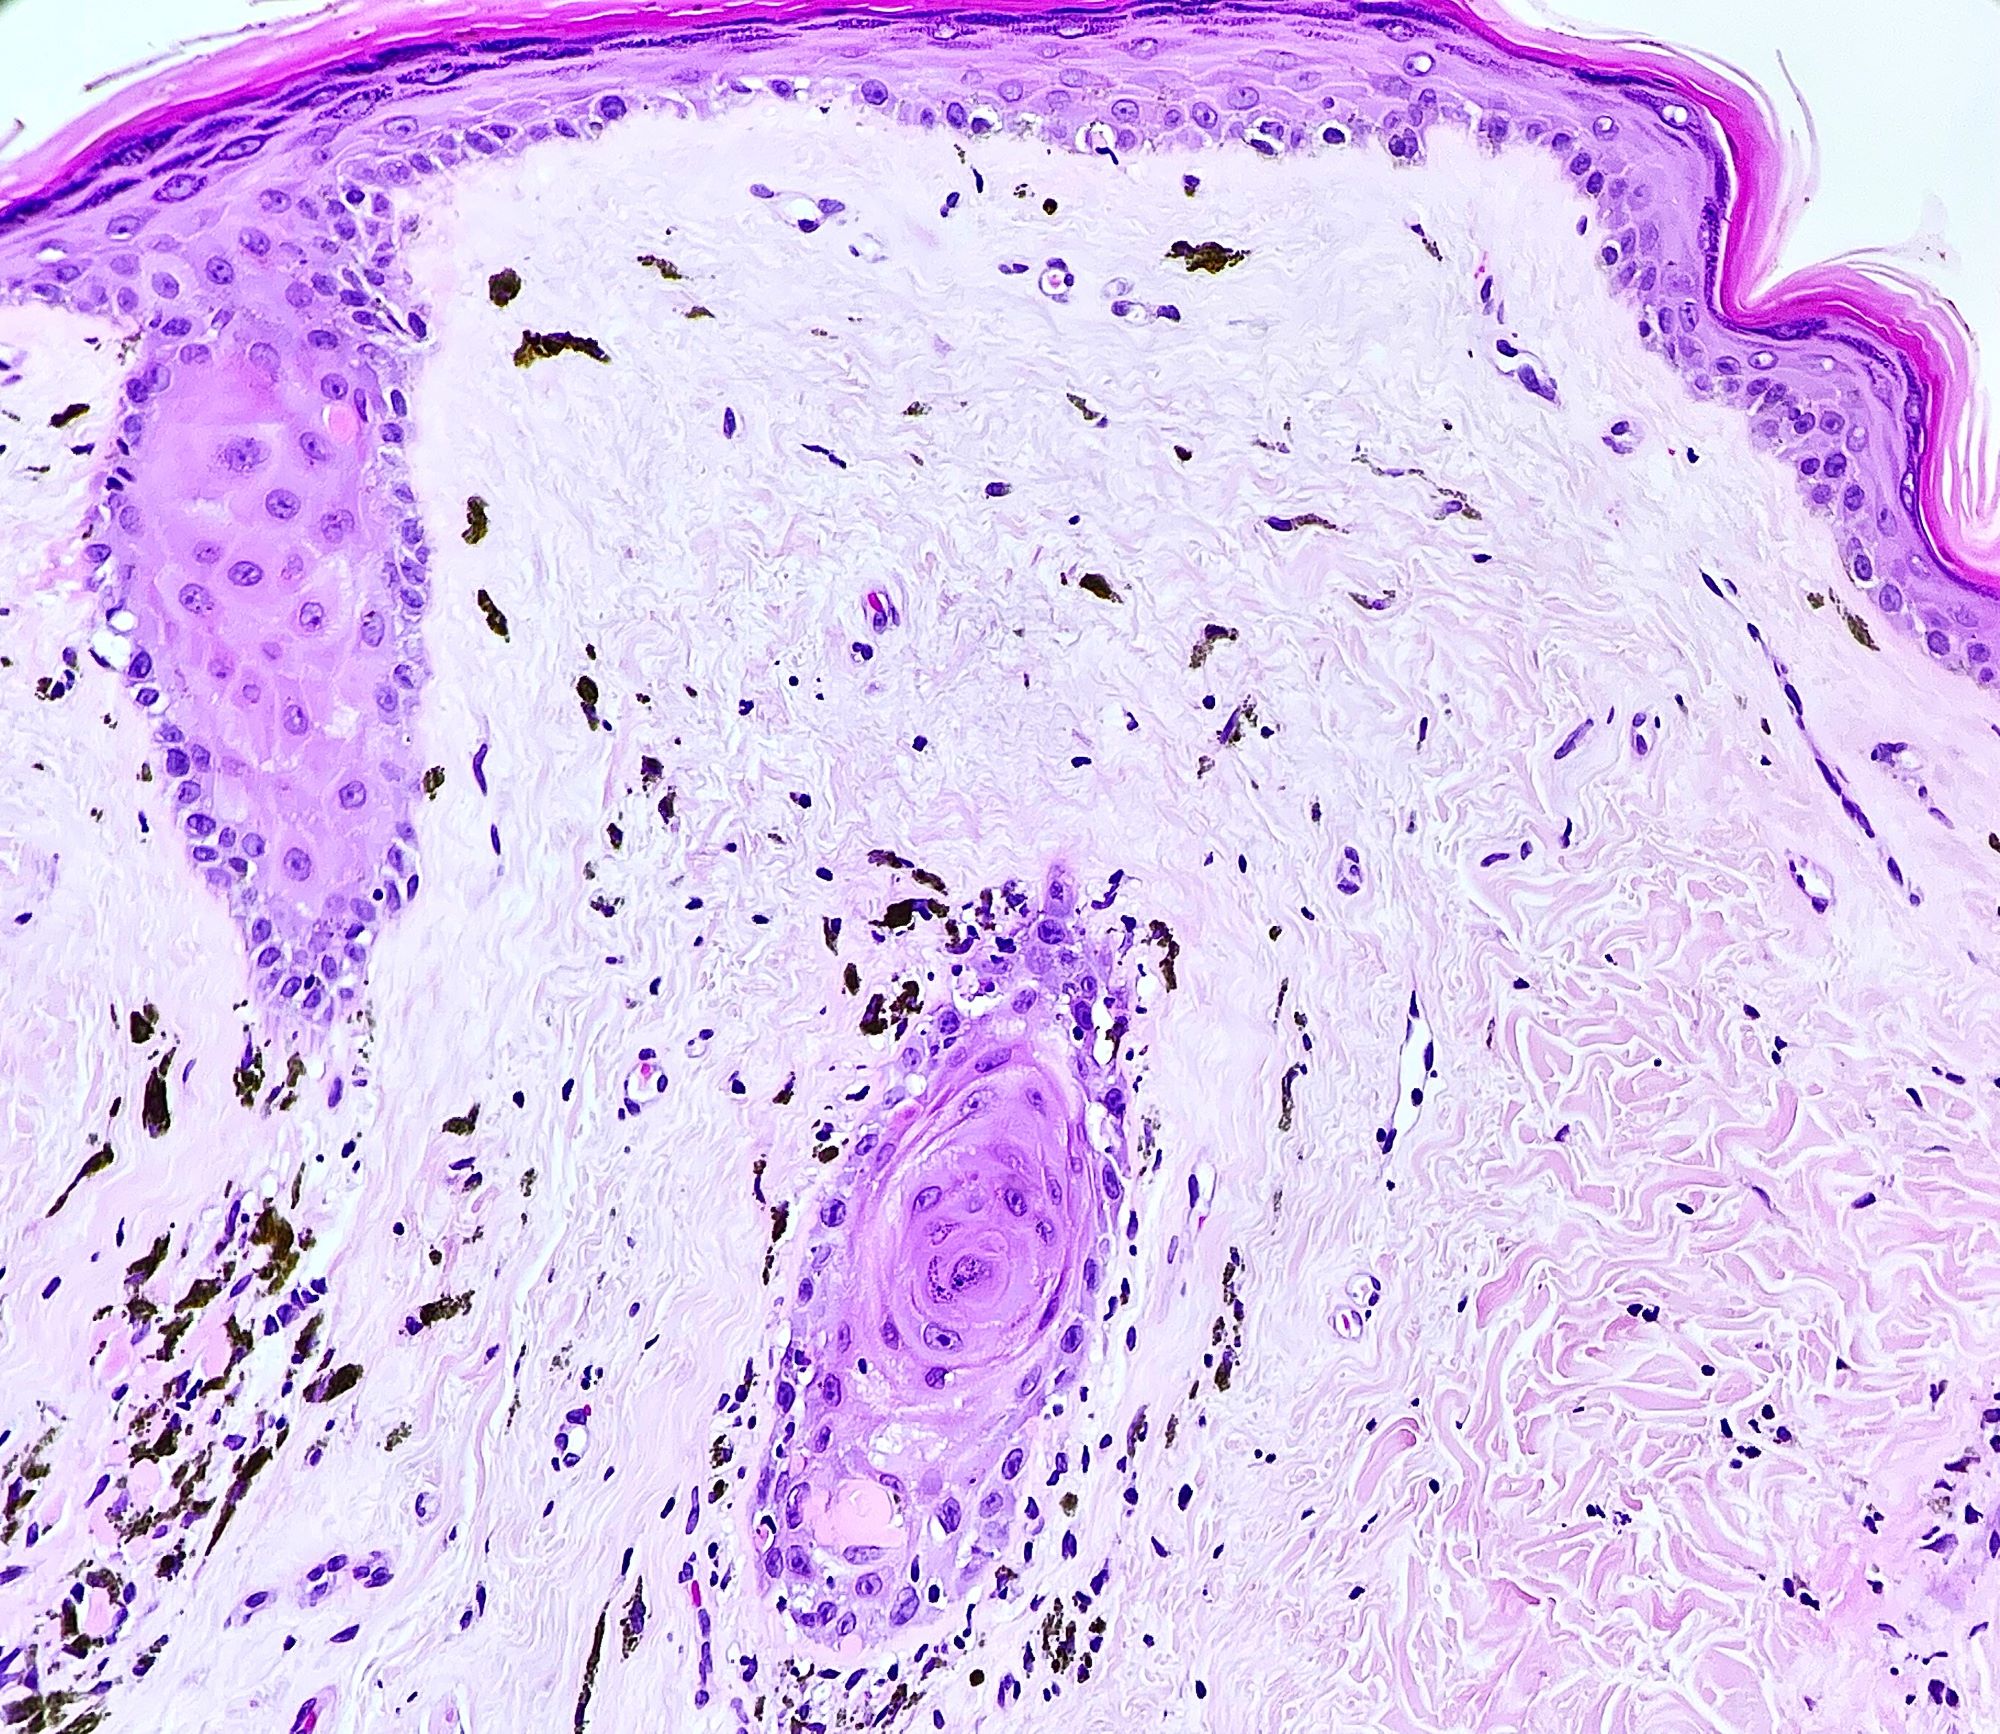

- Chronic GVHD (Biol Blood Marrow Transplant 2015;21:589, Patterson: Weedon's Skin Pathology, 4th Edition, 2015)

- Chronic sclerodermoid GVHD

- Dermal sclerosis (thickened compact collagen with loss of periadnexal fat)

- Manifests with localized morphea-like features, diffuse sclerosis or lichen sclerosus-like features

- Localized morphea-like features and diffuse sclerosis are largely confined to the reticular dermis or subcutaneous septa with little or no epidermal involvement

- Lichen sclerosus-like GVHD: collagen alteration is confined to the papillary dermis (hyalinzation of the papillary dermis), often with residual interface changes characterized by the presence of mild vacuolar alteration, melanophages and sparse superficial perivascular lymphocytic infiltrate

Microscopic (histologic) images

Contributed by Silvija P. Gottesman, M.D. and Ohoud Aljarbou, M.D.